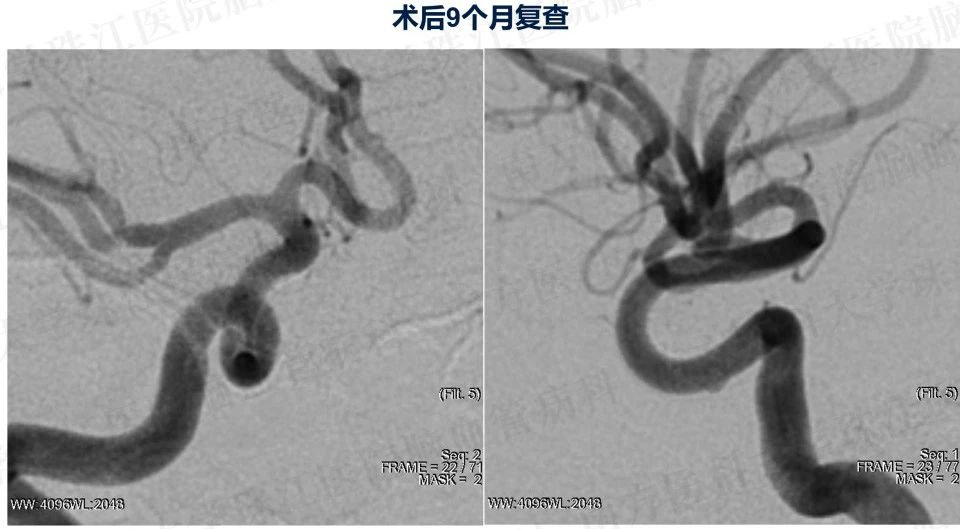

患者入院后造影发现“颈内动脉床突上段巨大动脉瘤,大小约2.7x3.5cm。决定行PIPELINES密网支架植入治疗。

患者入院后造影发现“颈内动脉床突上段巨大动脉瘤,大小约2.7x3.5cm。决定行PIPELINES密网支架植入治疗。